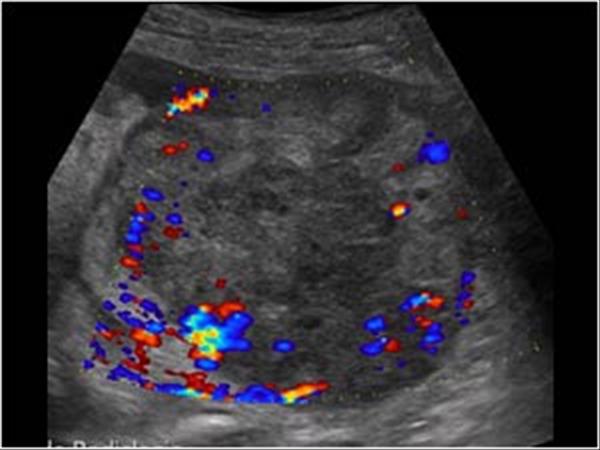

RCC

» Thông tin: Nữ giới – 69 tuổi.

» Lâm sàng: Đái máu.

# Ung thư biểu mô tế bào thận phải (Renal cell carcinoma – RCC) / Huyết khối tĩnh mạch chủ dưới.